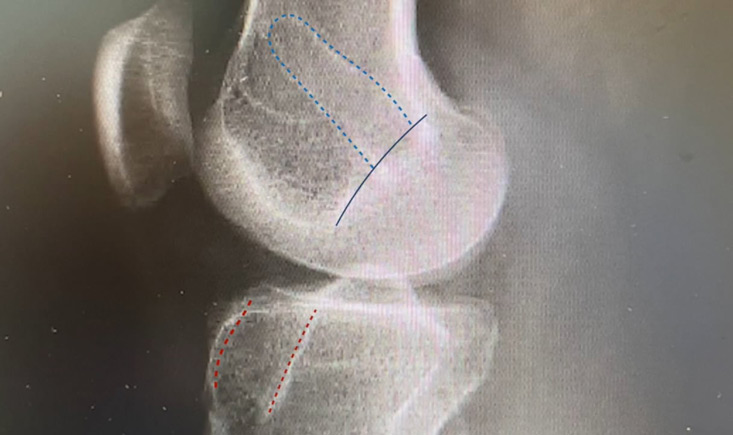

One-stage ACL revision using a bone allograft plug for a semianatomic tibial tunnel that is too anterior

Learn how to perform a one-stage ACL revision combined with lateral tenodesis using the IT band, specifically for cases where the tibial tunnel is too anterior in a semi-anatomic position.